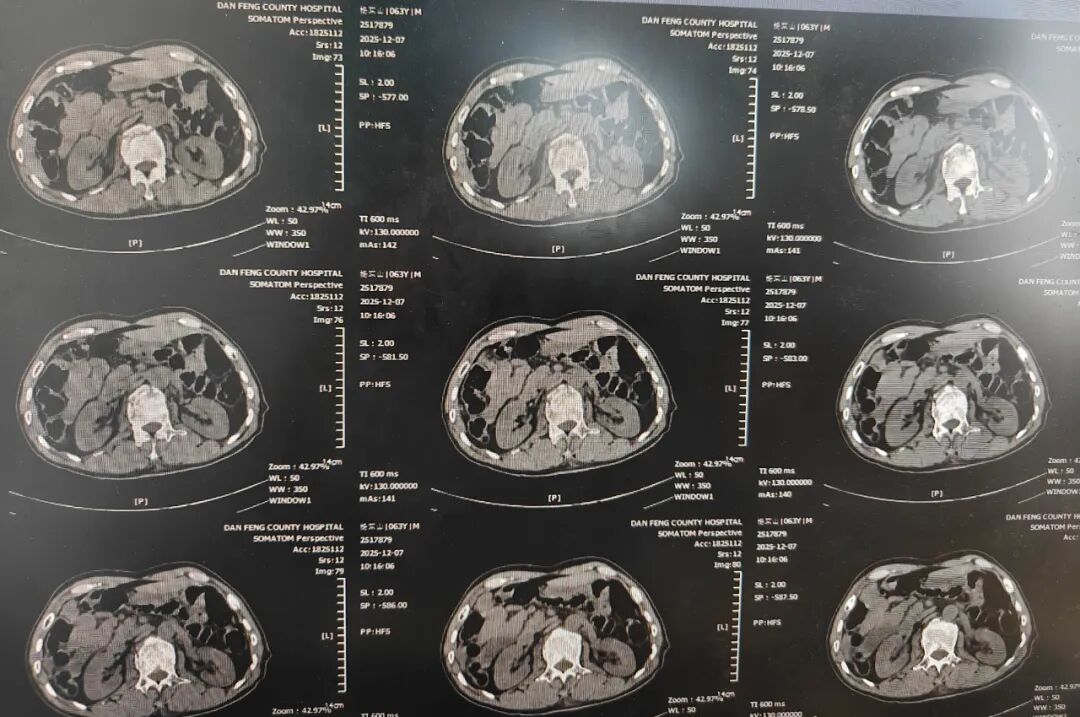

本次多学科讨论中,神经泌尿外科医师淡增增详细汇报了病例资料。患者男,64岁,因“车祸外伤后全身多处疼痛2小时”主诉于2025年12月6日19:30入院。入院诊断:1.急性中型闭合性颅脑损伤 创伤性蛛网膜下腔出血;2.胸部闭合性损伤 多发肋骨骨折 创伤性湿肺 血气胸;3.腰椎爆裂骨折;4.胸椎骨折;5.下颌骨髁突骨折;6.吸入性肺炎;7.应激性溃疡。